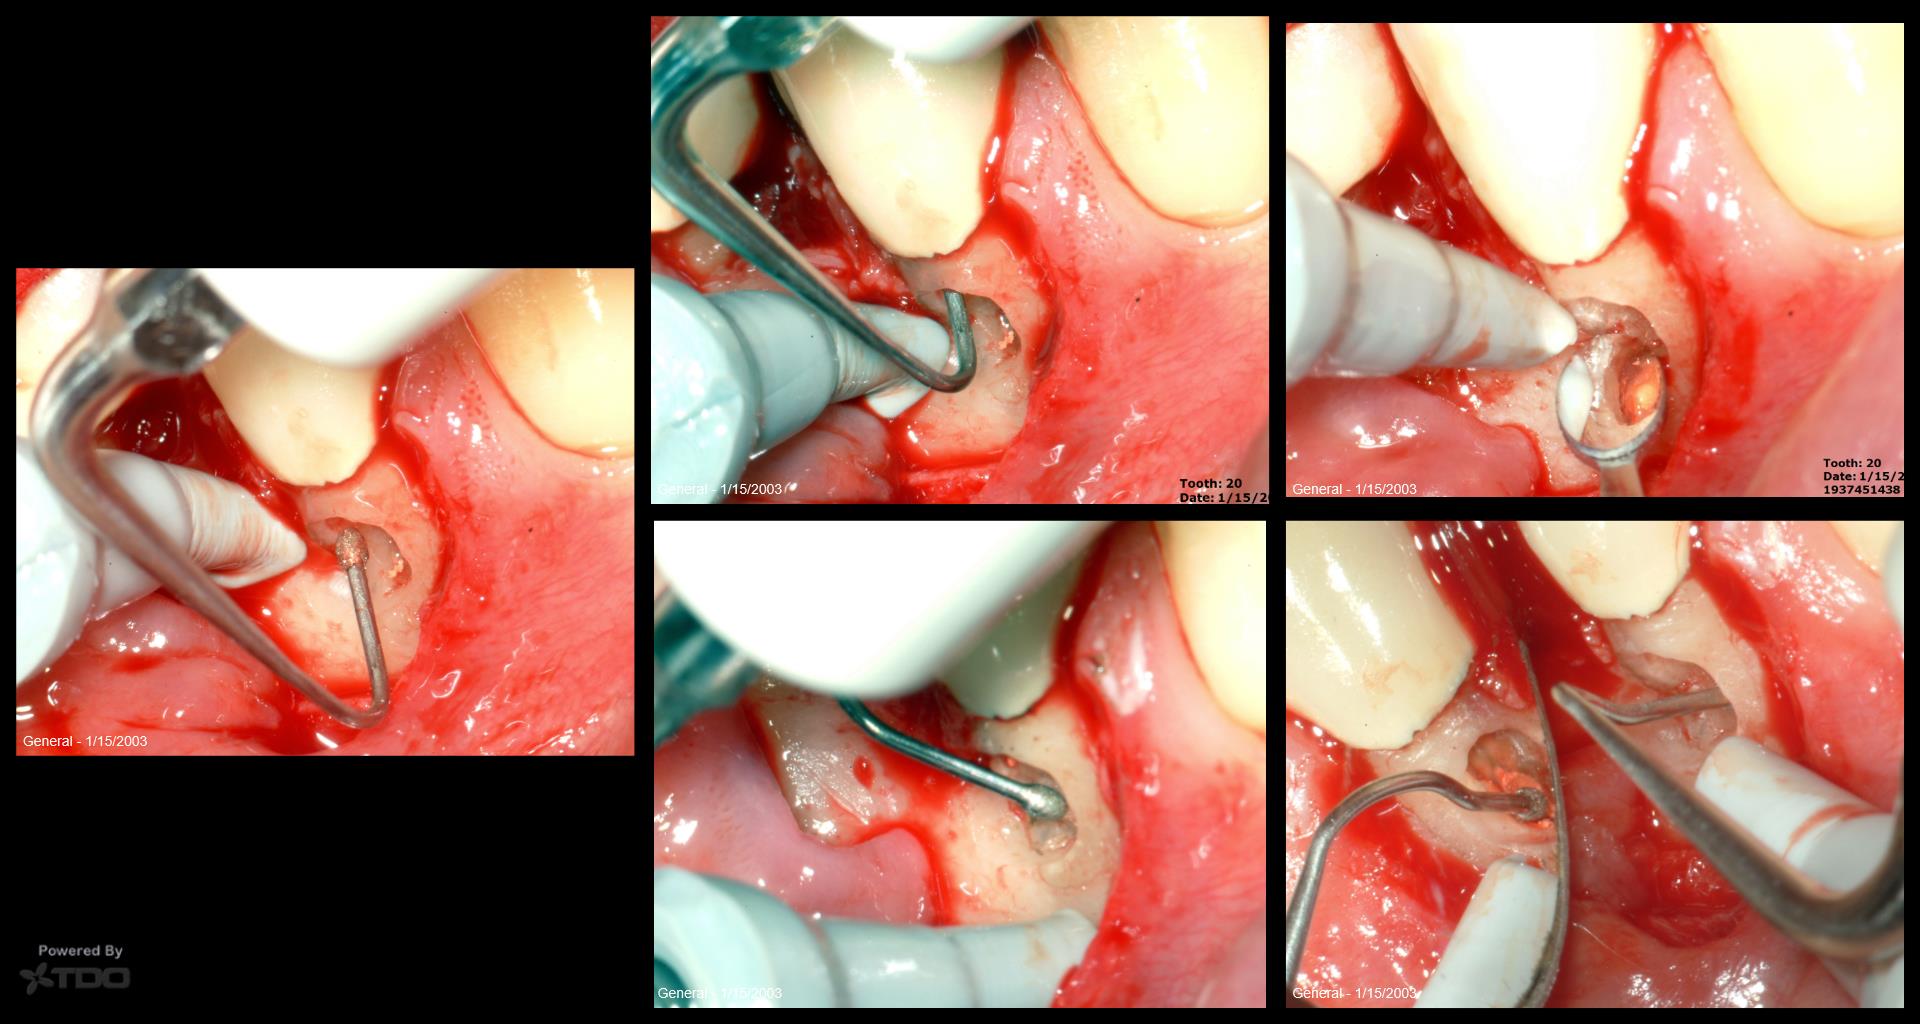

Probably not. When the CBCT shows the defect all on the buccal, I tend to go into hero mode….Today, I do what the patient tells me to do. I have a whole series of these now that we are monitoring. So far, I can’t think of a single one that suggests it is advancing. Maybe just dumb luck or no cats….